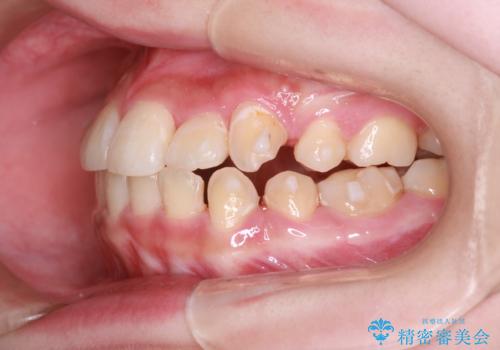

- 上下の前歯に激しい段差がある**重度の叢生(がたつき)**を主訴にご来院されました。精密検査の結果、歯をきれいに並べるためのスペースが圧倒的に不足していたため、上下左右の4番目の歯(第一小臼歯)を計4本抜歯する計画を立案しました。

ワイヤー矯正による先行治療: 最初のステージでは、ワイヤー装置を使用して抜歯したスペースへ歯を大きく移動させました。重度の叢生の場合、ワイヤーを用いることで歯のねじれや大きな移動をスピーディーに行うことができ、治療期間の短縮につながります。